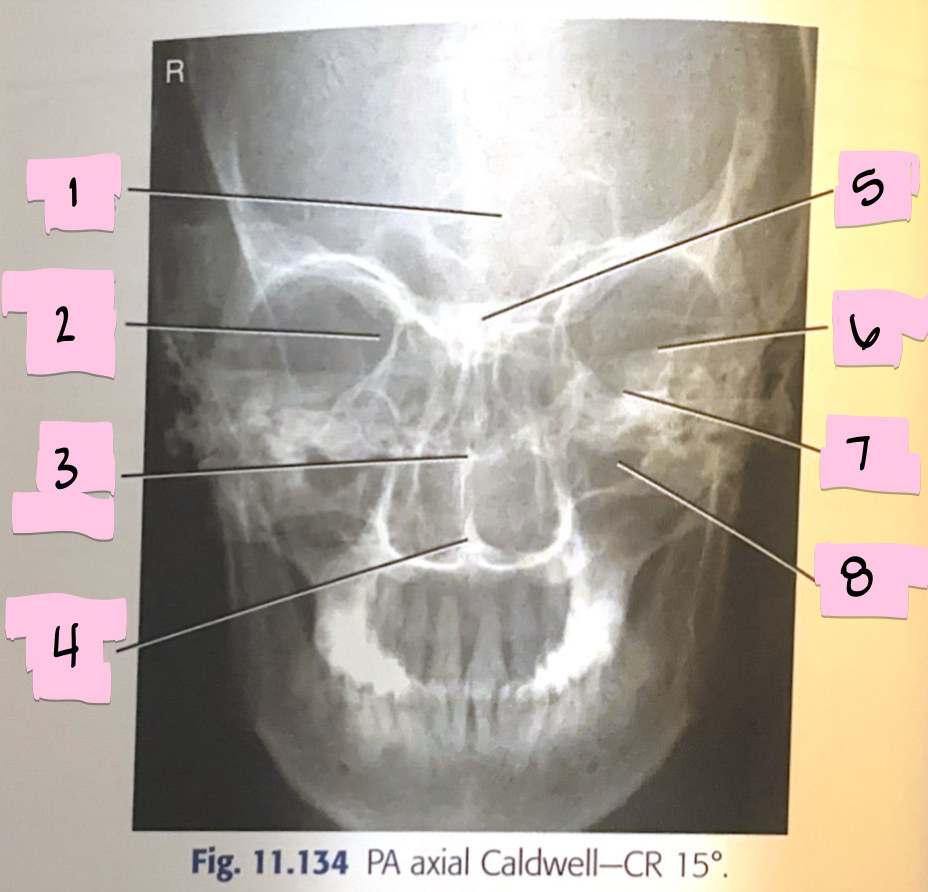

What is 1 pointing to?

Frontal sinus

What is 2 pointing to?

Superior orbital fissure

What is 3 pointing to?

Bony nasal septum

What is 4 pointing to?

Anterior nasal spine

What is 5 pointing to?

Crista galli

What is 6 pointing to?

Petrous ridge

What is 7 pointing to?

Floor of orbit

What is 8 pointing to?

Maxillary sinus